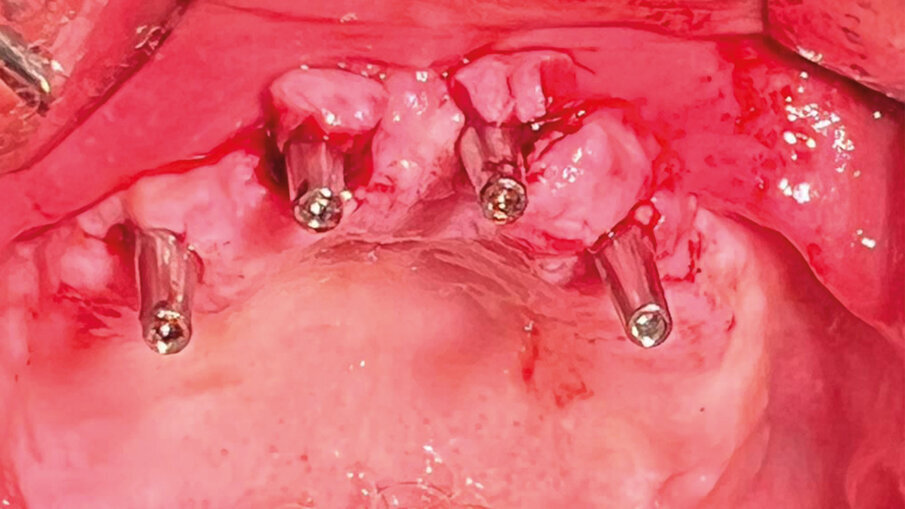

Fig. 5 - Foto durante l’inserimento del device.

Lo spessore della struttura del PD presenta 44 microfori passanti che permettono allo stesso di non fare effetto barriera tra l’osso basale e il periostio sovrastante. I dispositivi si distinguono in “a carico immediato” con i monconi monolitici senza connessioni da protesizzare subito; ed “a carico differito” cioè senza monconi ma con alloggiamenti filettati per permette di avvitare in un secondo momento quattro monconi per la protesizzazione (Fig. 1). Il procedimento chirurgico prevede una minima incisione da canino a canino, scheletrizzazione con distacco della parte terminale del nervo nasopalatino, come tutti i sottoperiostei, la modellazione dell’osso residuo con piezosurgery o fresoni per accogliere la forma del dispositivo ad appoggio completo e fissazione con impianti ridotti come detto sopra. La sutura sarà a completa copertura del PD a seconda se a carico immediato o differito prevede una seconda apertura solo sulle connessioni dei monconi che hanno delle viti tappo inserite (Figg. 2-15).